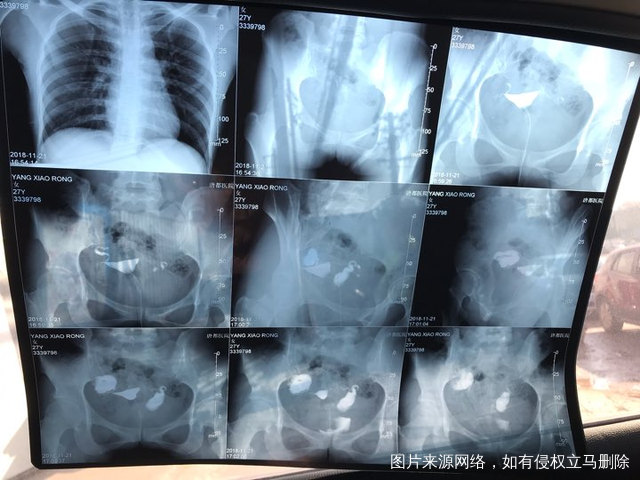

麻烦各位教授给我看看输卵管造影片子,谢谢了🙏